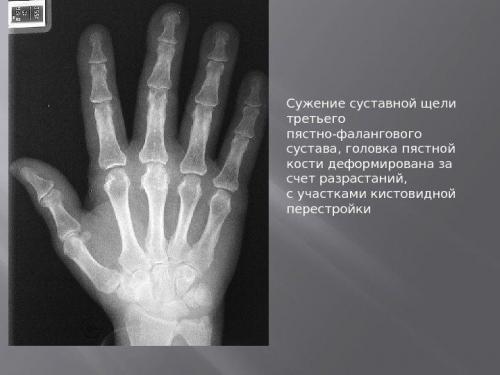

- Поверхность фаланг пальцев, оставшись без смазки, разрушается. Происходит «перерождение» костной ткани, образуются остеофиты – наросты, заметные на рентгеновском снимке.